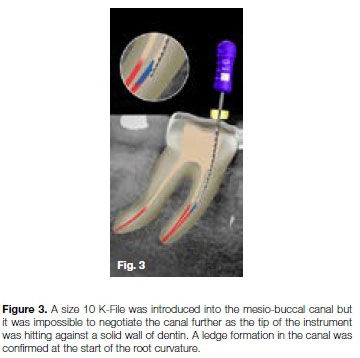

It was decided to use the Terauchi File Retrieval Kit (TFRFK) (Dental Cadre) to assist in removal of the fractured instrument. The 12 o'clock Micro-spoon ultrasonic tip (Figure 24) was used to penetrate through between the file and the canal wall in circular motion until it was noticed that the fractured file was loose in the canal. Considering the length of the fragment it was decided to attempt retrieval using the Yoshi Loop (Dental Cadre) (Figure 25a and 25b), a stainless steel micro-lasso that extends from the end of a stainless steel cannula attached to a handle with a retraction button for tightening the loop around the file segment.